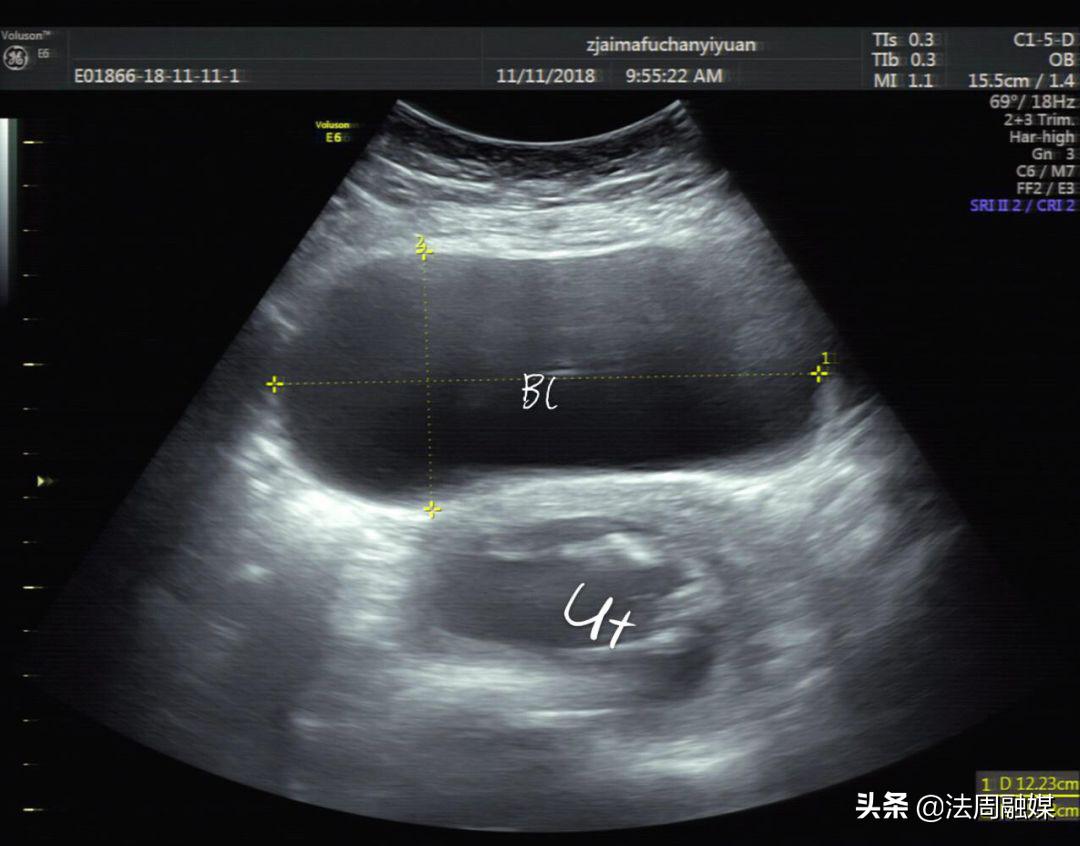

膀胱明显充盈表现细长,后方见妊娠子宫回声

子宫明显后倾后屈,宫颈细长